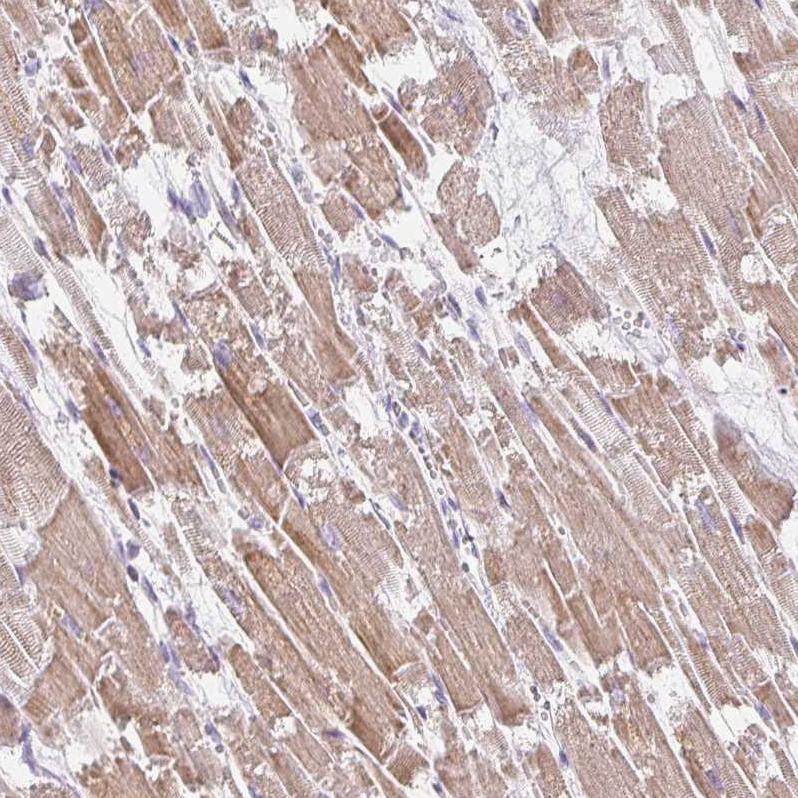

Immunohistochemical staining of human heart muscle shows moderate granular cytoplasmic positivity in cardiomyocytes.